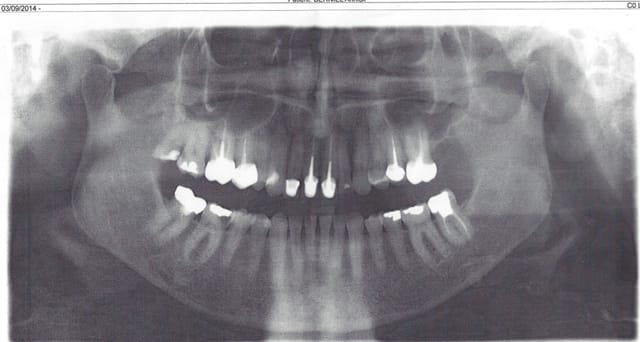

Ca par contre c'est normal. Pano fait dans un autre cabinet et soins aussi. Carie 46 pas de douleur et ......magie une endo IC coiffe en moins de temps qu'il ne faut pour le dire, patient solvabilisé dent défoncée. On a échappé à la peinture canalaire, ouf ! -)))))